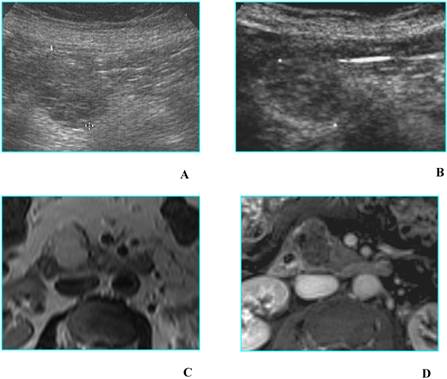

Fig 9

Malignant intraductal papillary mucinous tumor in a 80-year-old man who presented with obstructive jaundice. A. B-mode US shows a multilocular cystic lesion with mural nodules (calipers) located in the head of the pancreas. B. CEUS well depicts the vascularized septa and nodules in the lesion (calipers). Superior mesenteric artery (black arrow) and superior mesenteric vein (white arrow) are filled with contrast agent. C and D. MDCT on axial image (C) shows a multilocular lesion with a solid component; a stent is inserted in the common bile duct (arrow); on the curved reformatted image (D) the communication of the tumor with the pancreatic duct is demonstrated.

Int J Med Sci Image

d) Cysts with a solid component at B-mode US may be either unilocular or multilocular; true cystic tumors (MCN and IPMT) as well as solid tumors with a cystic component or cystic degeneration – primary or metastatic – are included in this category. All tumors of this group are either malignant or have a high malignant potential [12]; in these cases too CEUS does not offer a meaningful diagnostic contribution (Fig. 9).